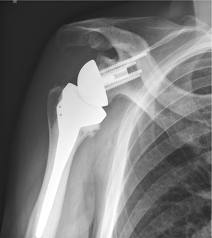

The reverse shoulder arthroplasty is a solution that directly addresses chronic deficiencies of a torn rotator cuff, compensating for its weakness or absence by rearranging the anatomy.

“In this procedure, the ball portion of the joint is taken from the humerus side and moved to the shoulder blade or scapula side and attached with an implant or prosthesis. The socket is moved to the upper end of the humerus side,” says Dr. Sabesan. “No other joint replacement surgery changes the normal anatomical structure like this.”

Like traditional shoulder replacement surgeries, the arthritic joint surfaces are replaced with a highly polished metal ball attached to a plastic socket, but in the reverse procedure, the socket and metal ball are switched. The reverse procedure constrains the ball in a cup that is inserted into the end of the humerus, and the metal ball is attached to the shoulder bone. The reversal increases tension of the deltoid muscle, producing more torque. In this way, the deltoid muscle compensates for the loss of rotator cuff by becoming the primary elevator of the shoulder joint and making it easier for a patient to raise his or her arm. Yet, range of motion remains limited.